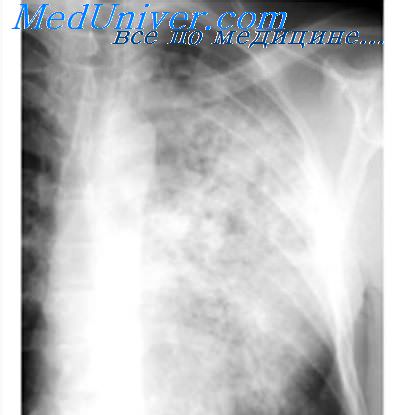

Во II стадии на фоне мелкоячеистого рисунка видны множественные мелкие узелковые тенеобразования, разбросанные довольно равномерно в обоих легочных полях на всём их протяжении, но больше в средне-нижних отделах. Контуры их чёткие. Элементы легочного рисунка как бы исчезают. Расширенные тени корней лёгких представляются как бы обрубленными от своих ветвей (симптом «обрубленного корня»), в дальнейшем могут подвергнуться сморщиванию. При переходе процесса во П стадию больной начинает ощущать выраженную одышку, больше выражен кашель, иногда боли в груди. Одышка медленно постепенно нарастает, развивается дыхательная недостаточность I-II степени.

В III стадии силикоза происходит слияние узелков, усиленное развитие соединительной ткани. При этом на рентгенограмме определяется наличие крупных фокусных образований, наряду с выра- женным фиброзом лёгких. В лимфатических узлах корня иногда можно обнаружить обыз- вествление по их наружному краю (симптом «яичной скорлупы»). В III стадии, когда фиброз и эмфизема увеличивается, развивается легочно- сердечная недостаточность.

II стадия силикоза, а особенно III — очень часто осложняется туберкулёзом — силикотуберкулёз. При силикозе чаще всего развивается очаговая, реже другие формы туберкулеза легких. Помимо этого, встречаются силикотуберкулезный бронхоаденит, узловой и так называемый массивный силикотуберкулез.

В отличие от туберкулёза, очаги при силикозе локализуются в латеральных частях средних отделов легочных полей, верхушечные области либо вовсе свободны, либо очаги находятся в них в небольшом числе. Очаговые тени при силикозе более интенсивны чем при диссеминированном туберкулёзе, контуры их более чётки

В то же время, в отличие от туберкулёза, во II-Ш стадии неосложнённого силикоза симптомы интоксикации не выявляются. Если к одышке, выраженному кашлю присоединяются симптомы интоксикации: повышение температуры, озноб, поты, похудание, повышение СОЭ, умеренный лейкоцитоз, лимфопения, уменьшение уровня альбуминов и нарастание глобулинов, то можно думать о развитии силикотуберкулёза. При этом рентгенологическое исследование позволяет выявить, наряду с силикозом, изменения, характерные для туберкулёза: наличие туберкулёзных очагов, инфильтратов, полостей распада. У большинства больных в мокроте обнаруживают БК.

Для диссеминированного туберкулеза, образующегося на фоне силикоза, характерна довольно типичная рентгенологическая картина.

В этих случаях туберкулезные очаги более полиморфны. Они располагаются преимущественно в верхних отделах легких, а под влиянием туберкулостатической терапии подвергаются более или менее выраженной инволюции. При хроническом диссеминированном туберкулезе очаги, как правило, различной плотности, определяются плевральные изменения, иногда отмечаются признаки цирроза легких. Недавно возникшие эластичные каверны на фоне узелкового силикоза имеют чаще неправильную округлую форму и выявляются более четко только на томограмме. Фиброзно-кавернозный туберкулез характеризуется наличием оформленных каверн с выраженными, фиброзными стенками. Однако следует иметь в виду возможность развития силикотических каверн, которые возникают в толще силикотических узлов. Они имеют неправильную щелевидную форму с неровными внутренними ландкартообразными очертаниями. Как правило, в них не виден уровень жидкости. В большинстве случаев формирование таких каверн связано с влиянием туберкулезной инфекции. Клинически при фиброзно-кавернозном туберкулезе отмечаются симптомы интоксикации, физические изменения в легких, часто имеет место бацилловыделение. Заживление каверн наблюдается редко даже при рациональной антибактериальной терапии. При этом на месте отдельных полостей могут образоваться силикотуберкуломы.

- Рентгенография легких. При силикотуберкулезе может отражать различную картину: на фоне диффузного крупно-сетчатого фиброза и типичных для силикоза симметричных узелковых высыпаний в средних и нижних долях появляются туберкулезные очаги, инфильтраты, силикотуберкуломы, каверны, преимущественно расположенные в верхушечных областях.